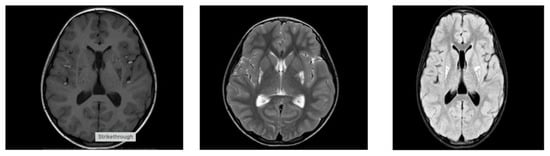

Biallelic variants in NDUFS6, encoding an accessory subunit of mitochondrial complex I, were initially associated with lethal neonatal mitochondrial encephalopathy and Leigh syndrome. Recent studies have demonstrated that NDUFS6 variants can also cause childhood- or adolescent-onset axonal neuropathy and Charcot–Marie–Tooth (CMT)-like phenotypes, indicating marked clinical heterogeneity. Here, we report a patient with a novel homozygous truncating NDUFS6 variant presenting with a neuropathy-predominant phenotype accompanied by epilepsy, in the absence of neonatal metabolic decompensation. The patient presented with childhood-onset progressive gait abnormality, pes cavus deformity, distal weakness requiring Achilles tendon-release surgery, pyramidal signs, urinary incontinence, and focal epileptiform EEG findings. Brain MRI showed bilateral lenticular nucleus abnormalities. Whole-exome sequencing identified a novel homozygous NDUFS6 nonsense variant (c.130C>T, p.Gln44*). While neuropathy has previously been reported primarily in association with the recurrent splice-site variant c.309+5G>A, our findings demonstrate that truncating NDUFS6 mutations can also underlie a neuropathy-predominant phenotype. Together with previously published cases, our findings support a phenotypic heterogeneity ranging from lethal encephalopathy to neuropathy and reinforce the role of NDUFS6 as a disease-causing gene for inherited peripheral neuropathy. These data support inclusion of NDUFS6 among established neuropathy and Charcot–Marie–Tooth genes. Full article

Figure 1